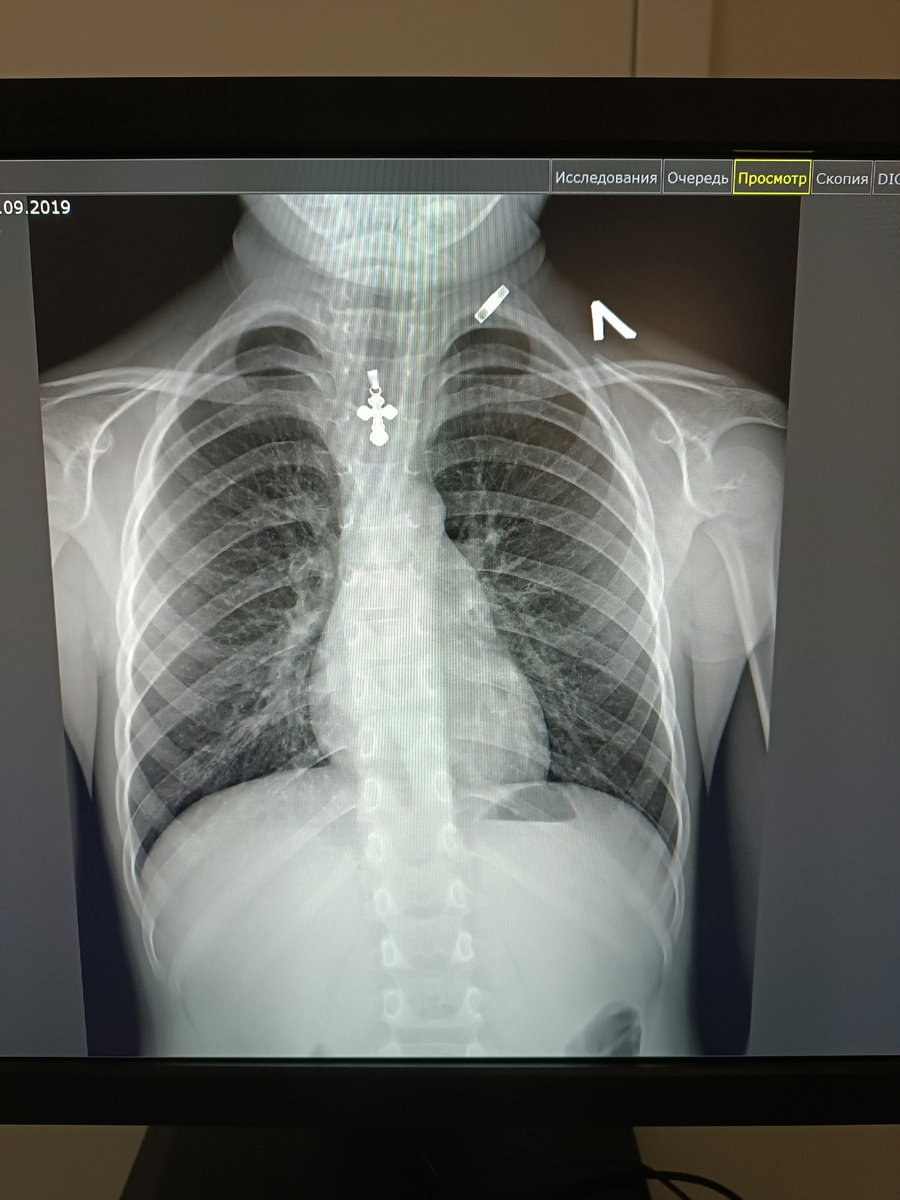

Врач, прослушав лёгкие Леши, сказала, что он не до конца выздоровел, есть хрипы, и желательно ему сделать рентген. На неделе в поликлинике были случаи атипичной, практически бессимптомной пневмонии у детей, а так как мы подвержены аллергии с периодическими обструктивными бронхитами, то лучше, на всякий случай, всё - таки лёгкие ребёнка проверить.

Его я забрала на регистратуре в субботу утром, приехала как она открылась. Переживала, так как хрипы врач всё же слышала. Развернув описание и пробежав его глазами, мой взгляд зацепился за диагноз : "Признаки острой пневмонии нижней доли правого лёгкого".

Оказывается, пневмония нижних долей лёгких самая труднодоступная, если так можно выразится. Лечат её только уколами антибиотика, ингаляциями и другими лекарствами и только в стационаре, так как необходимо круглосуточное наблюдение за ребёнком. Тогда уже окончательно испугалась и я. Врач ещё раз прослушала Лёшу и сказала, что низ лёгких прослушивается плохо, будто они в спазме. Нужно срочно ехать в больницу.

Посмотрела диагноз и стала заполнять информацию о симптомах в компьютер. На все её вопросы о вероятных симптомах по его самочувствию я отвечала отрицательно. Она была очень удивлена и начала слушать через стетоскоп грудную клетку Леши. Глаза врача становились всё больше, потому что никаких хрипов или спазмов она не слышала. Простучала - и также ничего не обнаружила.

Сверилась с диагнозом и сказала, что никакой пневмонии не видит. Направила нас на повторный рентген в Городскую больницу, предварительно позвонив заведующей и обрисовав ситуацию.

И действительно при повторном рентгене пневмонию нам не поставили, нашли лишь остаточные последствия бронхита.